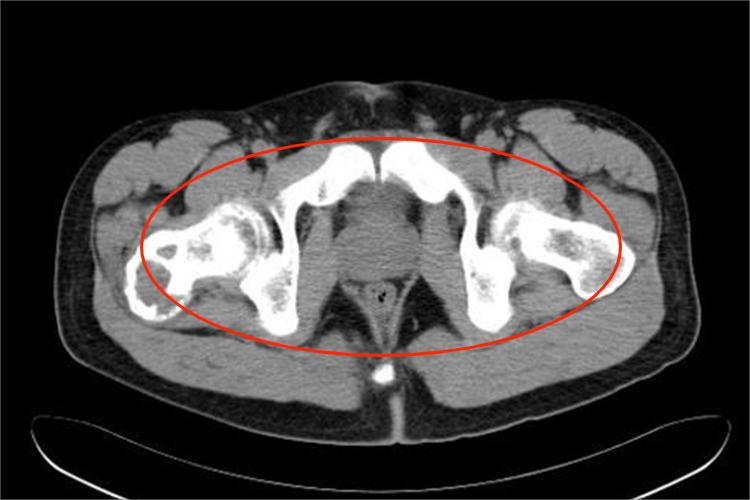

患者进行X线检查后,会发现病灶呈膨胀性囊状透亮区,与正常骨界面清楚并可有硬化边,病灶可位于骨干的中央,也可偏心生长。膨胀显著者可有薄骨壳,囊内有或粗或细的骨小梁状分隔或骨嵴,使病变成皂泡状外观。